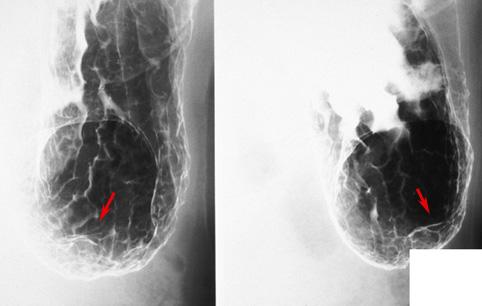

症例提示(所在地,施設名等): 福岡県・ 宗像医師会病院 (吉田道夫先生からの提供症例)

疾患(病理主体)の分類寄生虫疾患/アニサキス

部位(臓器別)胃(部位)/前庭

検査方法X-P

病変の最大径(ミリ)15〜19